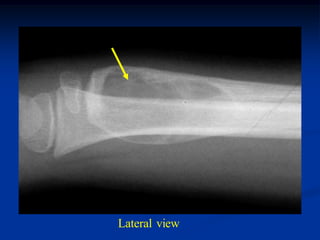

Case #989.3

12 year female with

unicameral bone cyst

distal femur

Lateral view

Coronal T-1 MRI

Coronal T-2 MRI

Axial T-1 MRI

Axial T-2 MRI